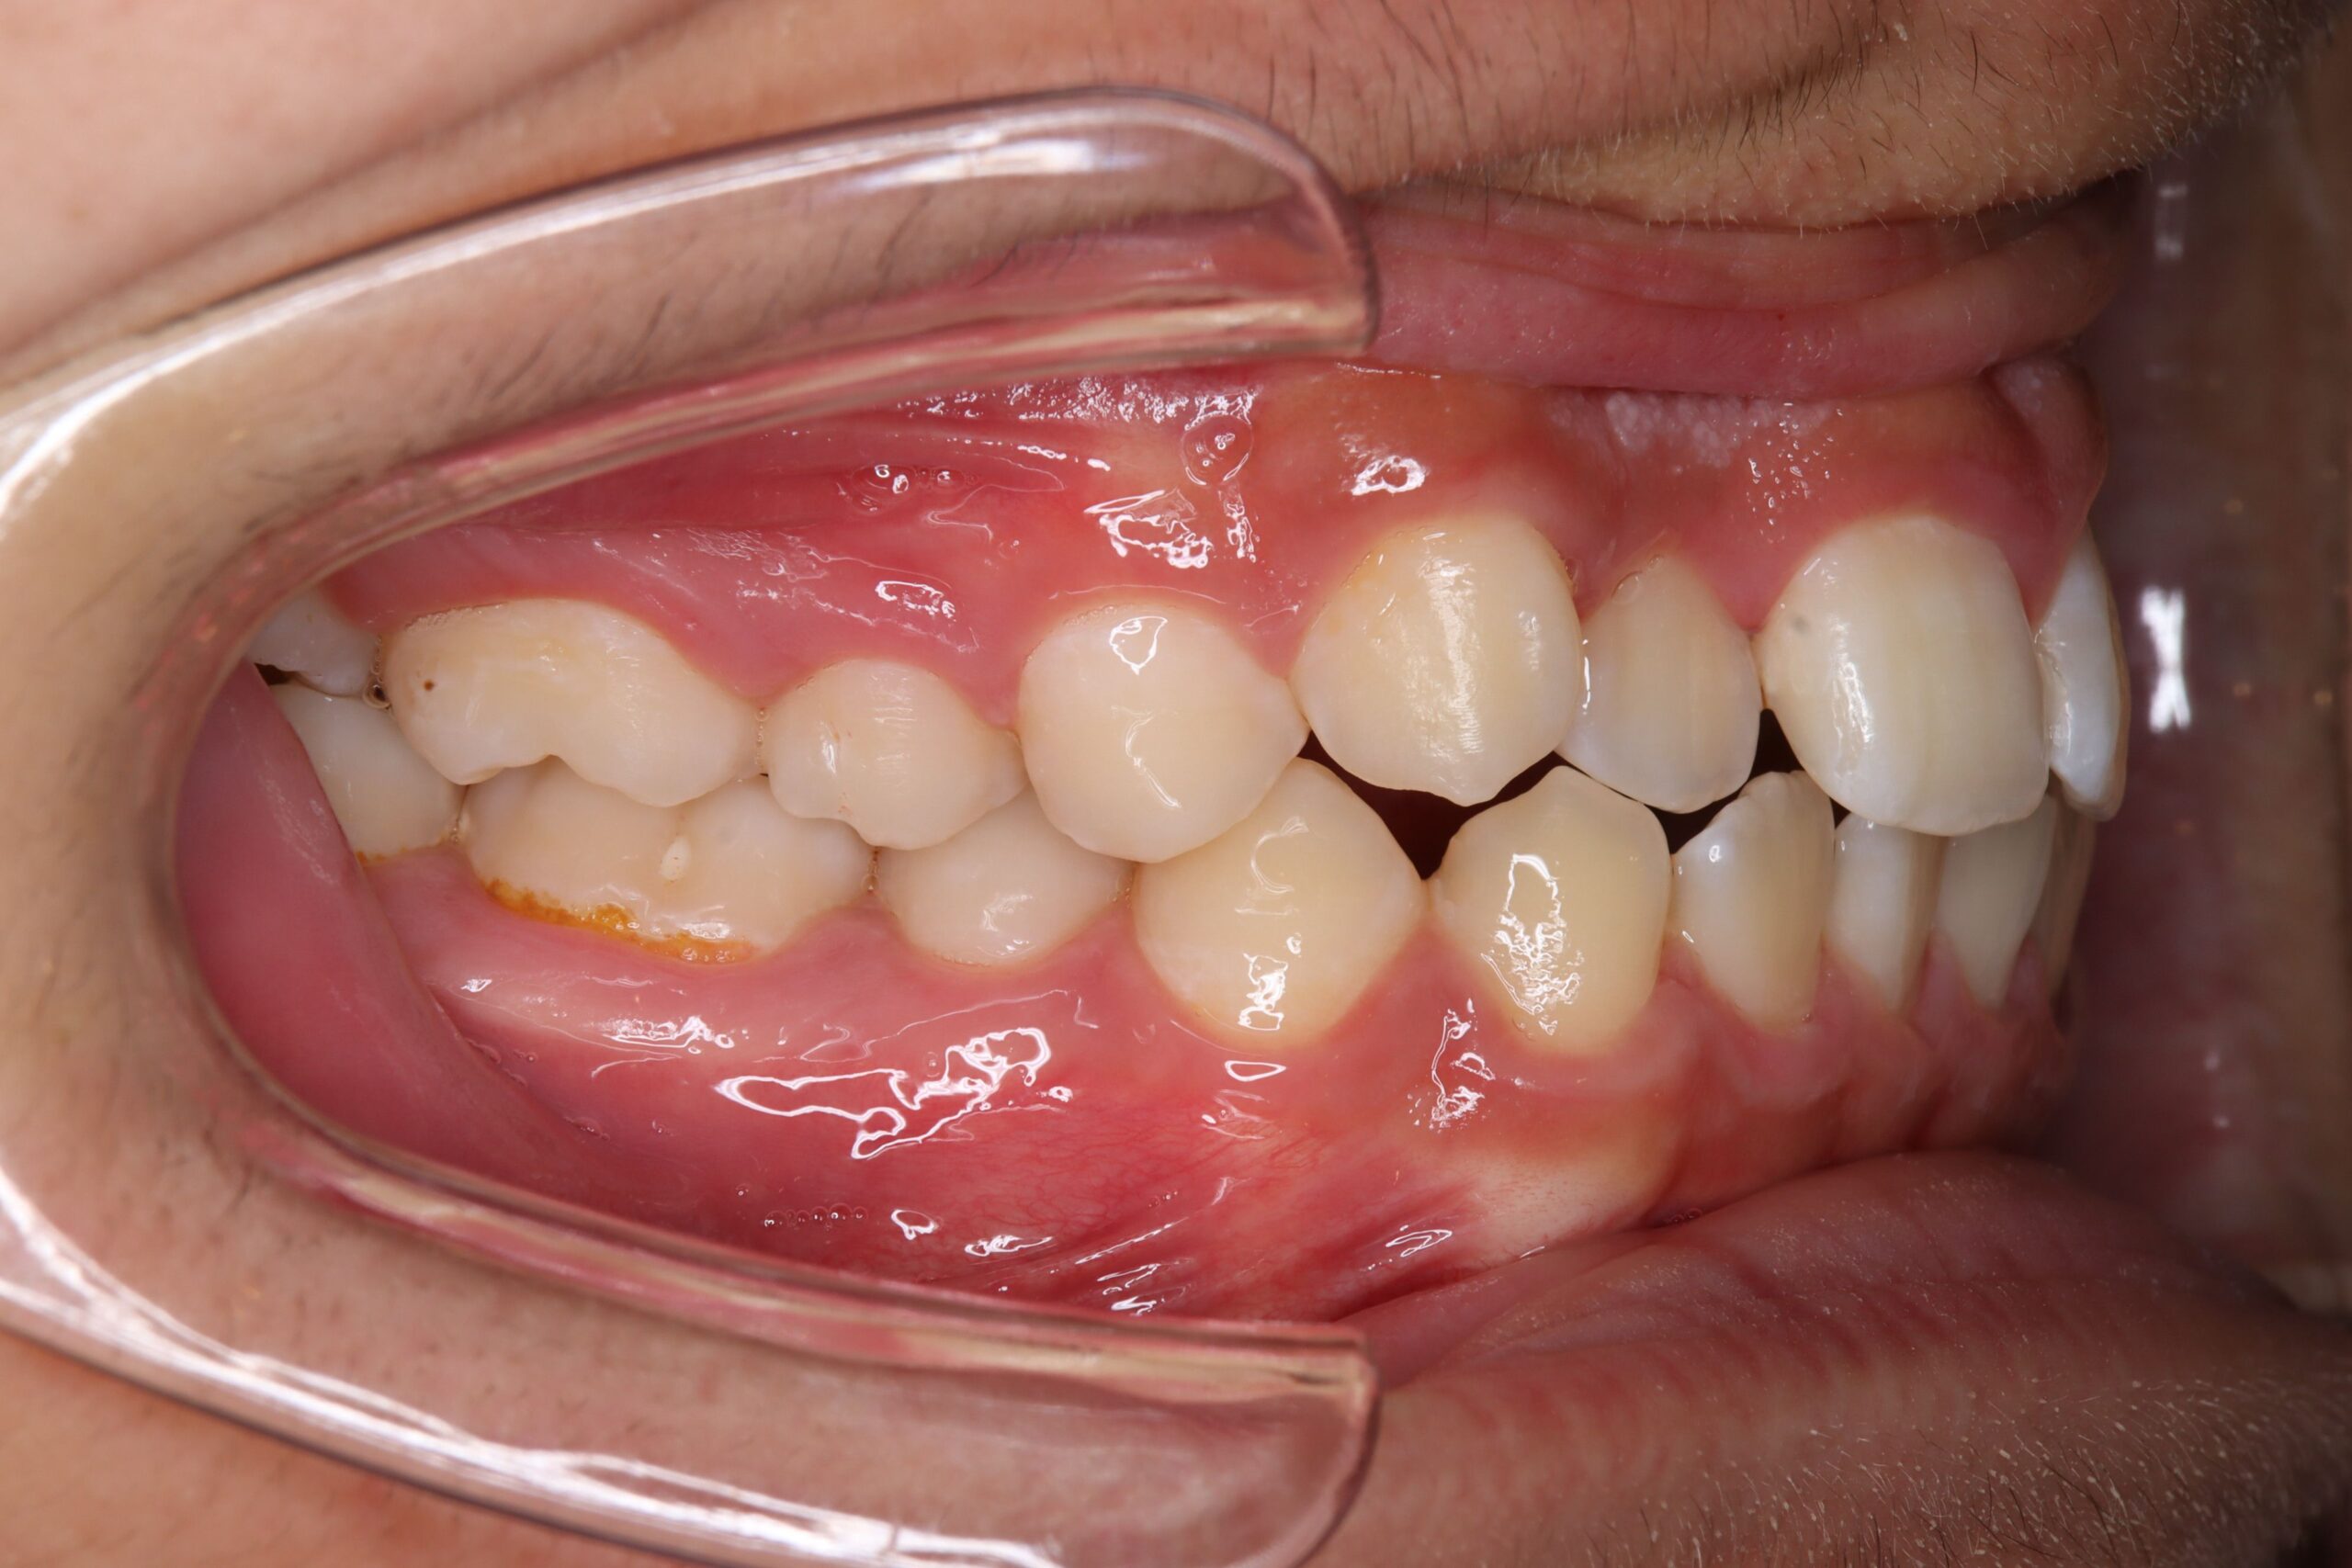

症例:非抜歯+アンカーで改善したケース

症例:ガタガタ+軽度の口元突出 → 非抜歯+アンカーで改善

非抜歯アンカー矯正の初診時|奈良の矯正歯科

初診時

インプラントアンカーで上の歯列全体を後方に移動。抜歯せずにガタガタと口元の突出感を改善しました。

ℹ️ ただし、この方法には限界があります。歯を後ろに動かせる量には上限があるため、口元の突出が大きい場合やガタガタが重度の場合は、非抜歯では対応できません。適応かどうかは精密検査で判断します。